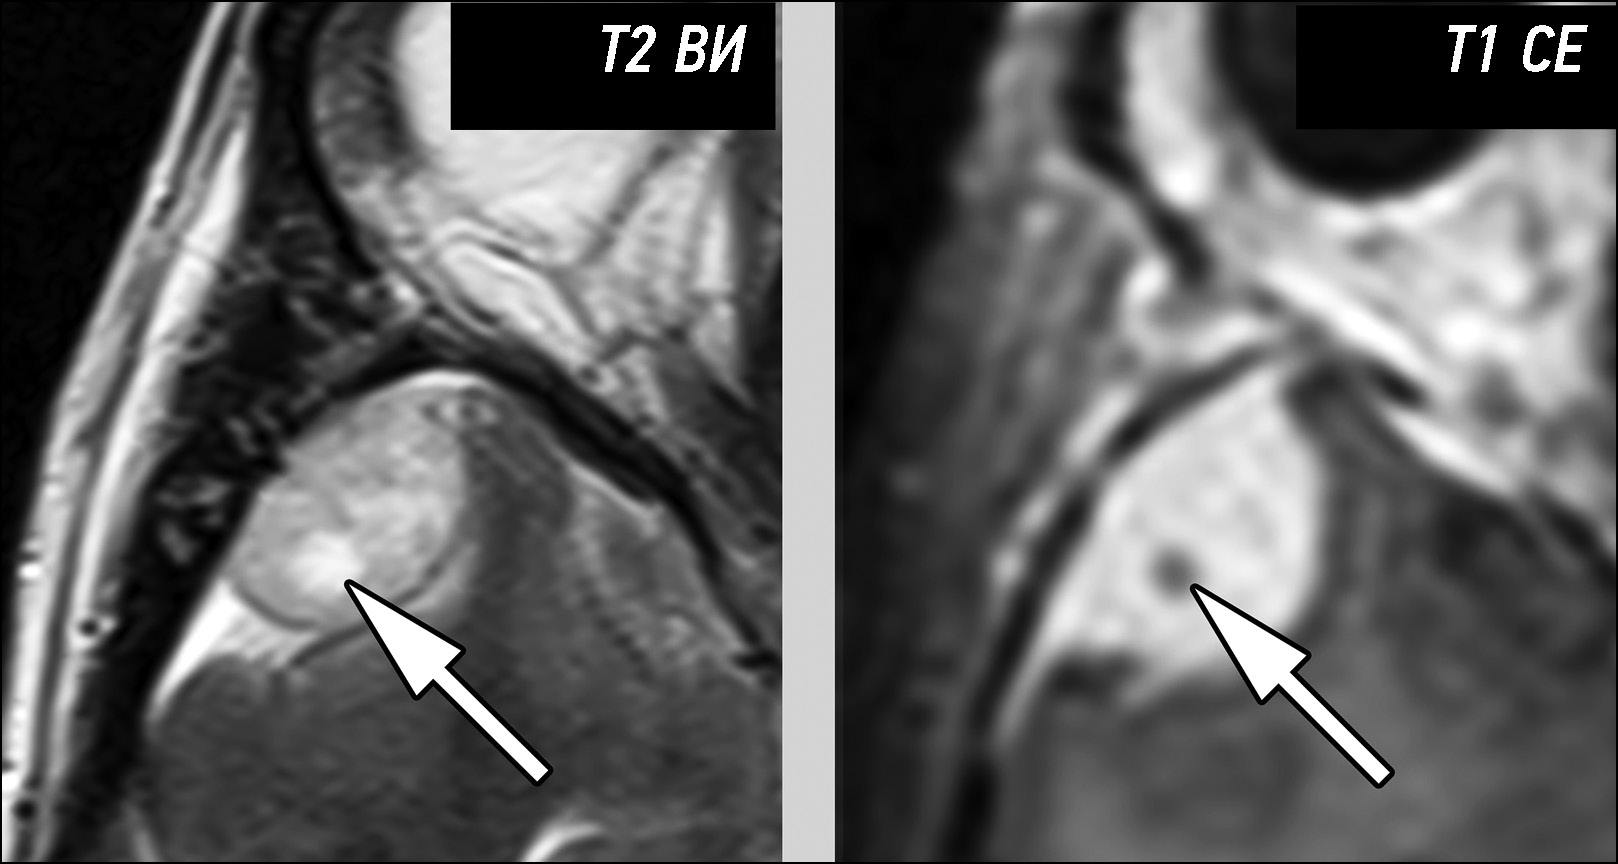

Первичные внемозговые опухоли представлены доброкачественными и злокачественными новообразованиями мозговых оболочек и черепных нервов. Их предоперационная дифференциальная диагностика основана на анализе семиотики магнитно-резонансной томографии. Критически важными моментами, позволяющими классифицировать опухоли данной группы, являются следующие признаки: структура образования, характер контрастирования, отграничение образования от мозговой ткани, наличие взаимосвязи с мозговыми оболочками или черепными нервами.

Провести дифференциальную диагностику различных типов первичных внемозговых опухолей на основе визуального анализа данных магнитно-резонансной томографии в большинстве случаев, при типичных признаках семиотики, не представляет затруднений. При атипичных проявлениях на магнитно-резонансной томографии надёжное разграничение опухолей бывает затруднительно. Наибольшую сложность при этом представляет дифференциация менингиом различной степени злокачественности, разграничение солитарных фиброзных опухолей и менингиом и установление типа опухоли при её локализации в мостомозжечковых углах.

Представлена серия наблюдений, содержащая наиболее типичные ситуации, приводящие к ошибкам дифференциальной диагностики первичных внемозговых опухолей на основании данных магнитно-резонансной томографии. Все представленные образования были верифицированы по результатам постоперационного гистологического исследования.